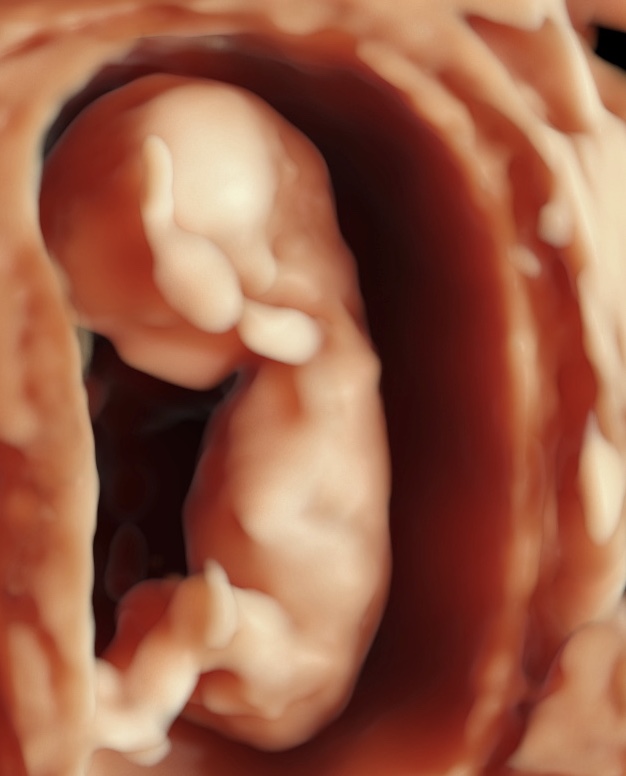

Somos expertos en detección temprana de anomalías. Brindamos una gama completa de Ultrasonidos Fetales y Ecografías 5D-7D: